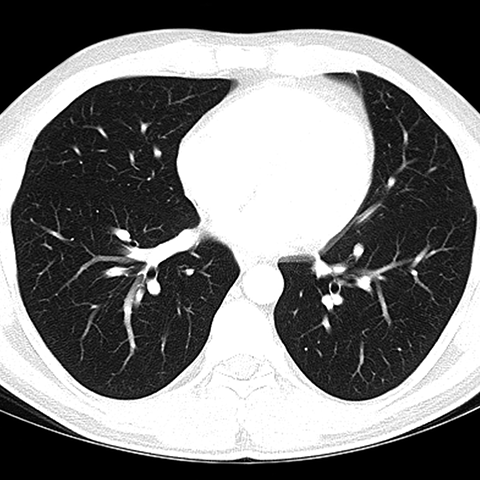

CT of Normal Trachea and Bronchi [5 of 5]